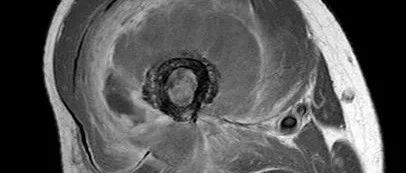

软骨肉瘤好发于骨盆, 也可发生在股骨、胫骨等长骨的干骺端和肩胛骨等处。而发生于肋骨者少见, 我科收治了 1 例肋软骨肉瘤, 现报告如下。病例资料患者,女,48 岁,系体检发现左第六后肋肿物入院。图 A、B:术前 CT、MR 检查胸椎 CT 检查提示:左第六后肋肿物,骨巨细胞瘤细胞瘤待排。MR 示:T6 椎体水平左侧脊柱旁占位灶,考虑骨巨细胞瘤细胞瘤可能大 (图 A、B)。术前血常规、凝血、肝肾功能、肿瘤标志物未见异常,行 CT 下定位并标记,因肿物靠近胸主动脉,邀请胸外科联合手术治疗,排除手术禁忌后,于 2018 年 3 月 19 日在全麻下行左第六后肋肿物扩大切除术。...